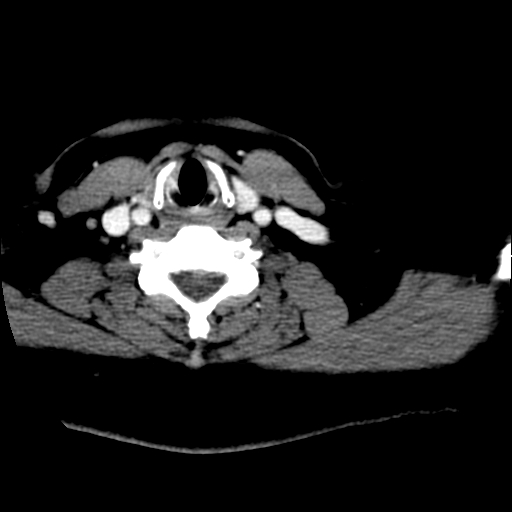

腺瘤囊变

考虑左侧甲状腺腺瘤囊变。

甲状腺腺瘤